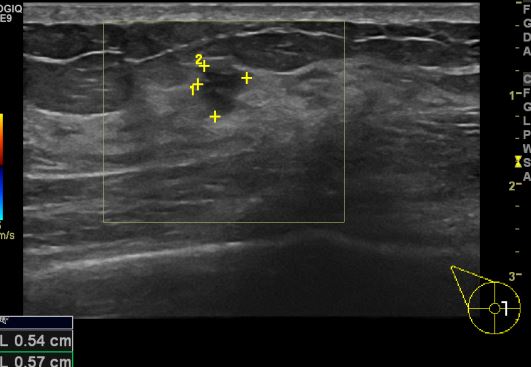

상기환자 유방의 통증으로 내원하신 40대 여성 분으로 우측 3시 방향 의심되는 혹

조직검사 시행하여 비정형 세포 관측되어 맘모톰 시행한 결과 우측 침윤성 유관암 진단 되었습니다.